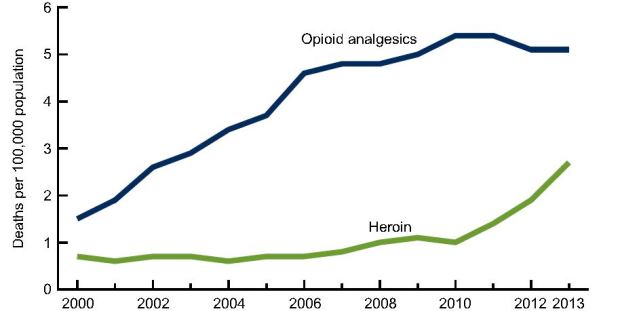

The age-adjusted rate for drug overdose deaths involving heroin jumped from 0.7 deaths per 100,000 in 2000 to 2.7 deaths per 100,000 in 2013, according to a new CDC report, and most of the increase occurred after 2010.